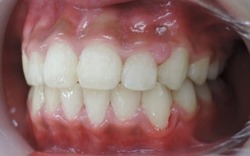

☆治療終了時

永久歯を抜歯する事無く治療を完了する事が出来ました。

咬合高径の改善、前歯の審美的改善のためにMEAW法(マルチループ)を使用しています。